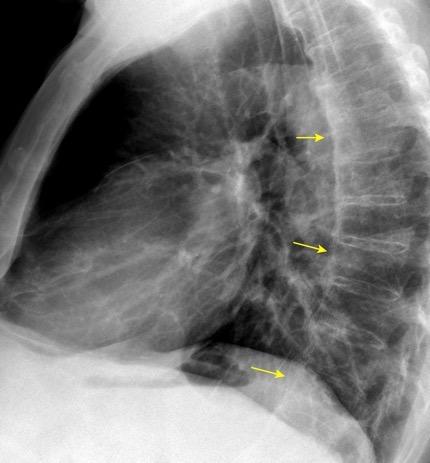

T. mixto de células

Ganglios retroperitoneales (flechas negras)

germinales del testículo izquierdo Nódulos pulmonares múltiples. (flechas verdes). Ganglios paratraqueales. (flechas amarillas). Dudoso ensanchamiento retrocrural (flechas negras)

Panda A et al. “Straddling Across Boundaries”. Thoracoabdominal Lesions: Spectrum and Pattern Approach. Curr Probl Diagn Radiol, 2015